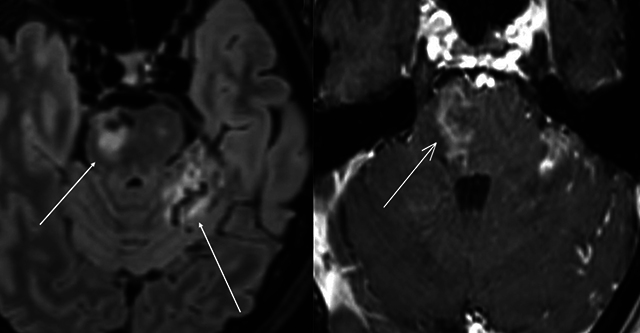

Carotid-cavernous fistulas (CCFs) are abnormal connections between the carotid arteries and the cavernous sinus, posing significant neuro-ophthalmologic risks. This report presents a rare case of bilateral post-traumatic CCFs, focusing on clinical presentation, diagnosis, and management. Symptoms mimic conjunctivitis, causing diplopia, exophthalmos, and ophthalmoplegia. Diagnosis relied on computed tomography, magnetic resonance angiography, and digital subtraction angiography. Management involved transarterial embolization with coils, achieving successful outcomes. This highlights the importance of timely intervention and comprehensive imaging to prevent complications. Teaching point: This case report details a rare instance of bilateral post-traumatic carotid-cavernous fistulas, emphasizing clinical presentation, diagnostic evaluation, and management.

颈动脉海绵窦瘘(CCFs)是颈动脉和海绵窦之间的异常连接,对神经眼科构成重大风险。本报告介绍了一例罕见的双侧外伤后 CCF 病例,重点阐述了临床表现、诊断和处理方法。症状类似结膜炎,导致复视、眼球外翻和眼肌麻痹。诊断主要依靠计算机断层扫描、磁共振血管造影和数字减影血管造影。治疗包括使用线圈进行经动脉栓塞,取得了成功。这凸显了及时干预和全面成像对预防并发症的重要性。教学要点:本病例报告详细介绍了一个罕见的双侧创伤后颈动脉海绵瘘病例,强调了临床表现、诊断评估和处理方法。